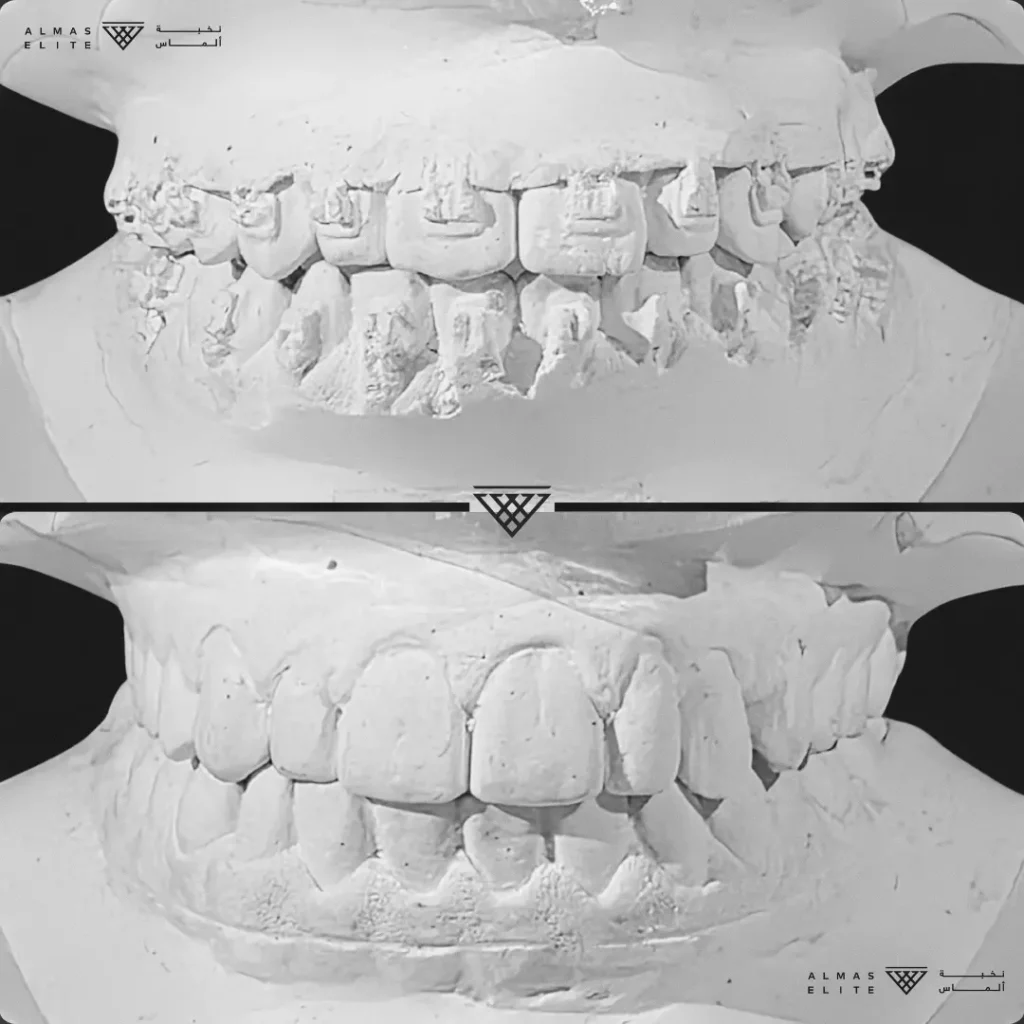

مراحل علاج التقويم

١) المرحلة التحضيرية قبل التقويم

تشمل علاج التسوس، خلع الأسنان غير المناسبة إن لزم، تنظيف الأسنان العميق، وعلاج اللثة عند الحاجة.

هذه المرحلة ضرورية ولا يمكن بدء العلاج بدونها في كثير من الحالات.

٢) التقييم والتشخيص الشامل

يشمل صور الأشعة والتحليل الرقمي للأسنان والفكين للوصول إلى تشخيص دقيق.

٣) وضع خطة علاجية مخصصة

تتضمن نوع الجهاز الأنسب، المدة المتوقعة، وتكلفة العلاج، مع شرح واضح لما يمكن توقعه أثناء رحلة التقويم.

٤) التركيب والمتابعة

يتم تركيب الجهاز والمتابعة بزيارات دورية غالبًا كل 3–6 أسابيع حسب الخطة العلاجية.

٥) المرحلة النهائية

إزالة الجهاز وتركيب المثبتات للحفاظ على النتيجة واستقرار الأسنان.